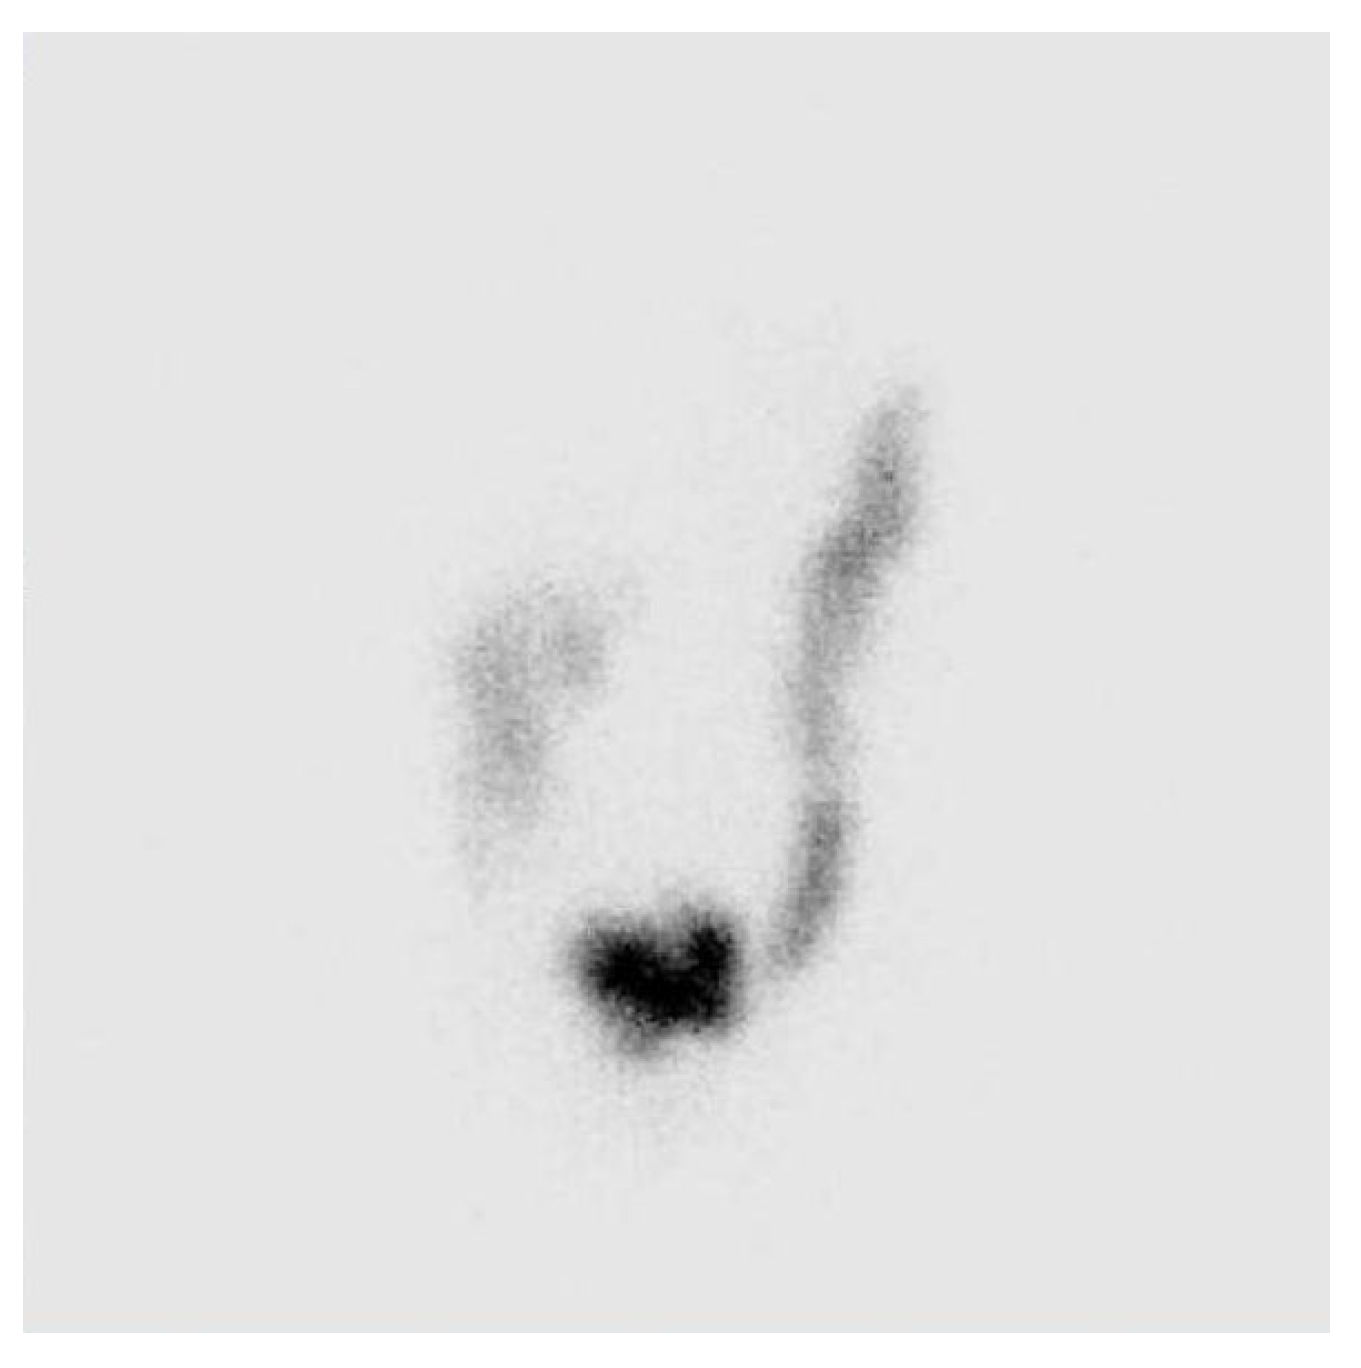

The qualitative assessment yielded the following results: The majority of examined patients with symptomatology I after self-evaluation indicating constipation showed a generalized slowed transit time through the large intestine. By general analysis between genders, it was observed that generalized slowing of colonic transit was detected more often in women compared to the male part of the examined patients. In 85% of women, a significant slowing of colonic transit was observed after the scintigraphic study, while 15% of subjects showed both qualitatively and GC-estimated normal colonic transit. In men, slowed colonic transit was detected in 78% of examined patients, while 22% of patients had qualitatively normal colonic transit and GC that fell within normal values. In women, the slowing down of colonic transit in the transverse and descending colon predominated, Figure 1 and Figure 2.

Figure 1. Static scintigram in anterior projection, 48 hours after administration of radiofarmaceutical. Female 48 years old, with constipation symptomatology. Qualitatively retention of radiopharmaceutical was observed in transverse and descending colon. GC value was 2,4.